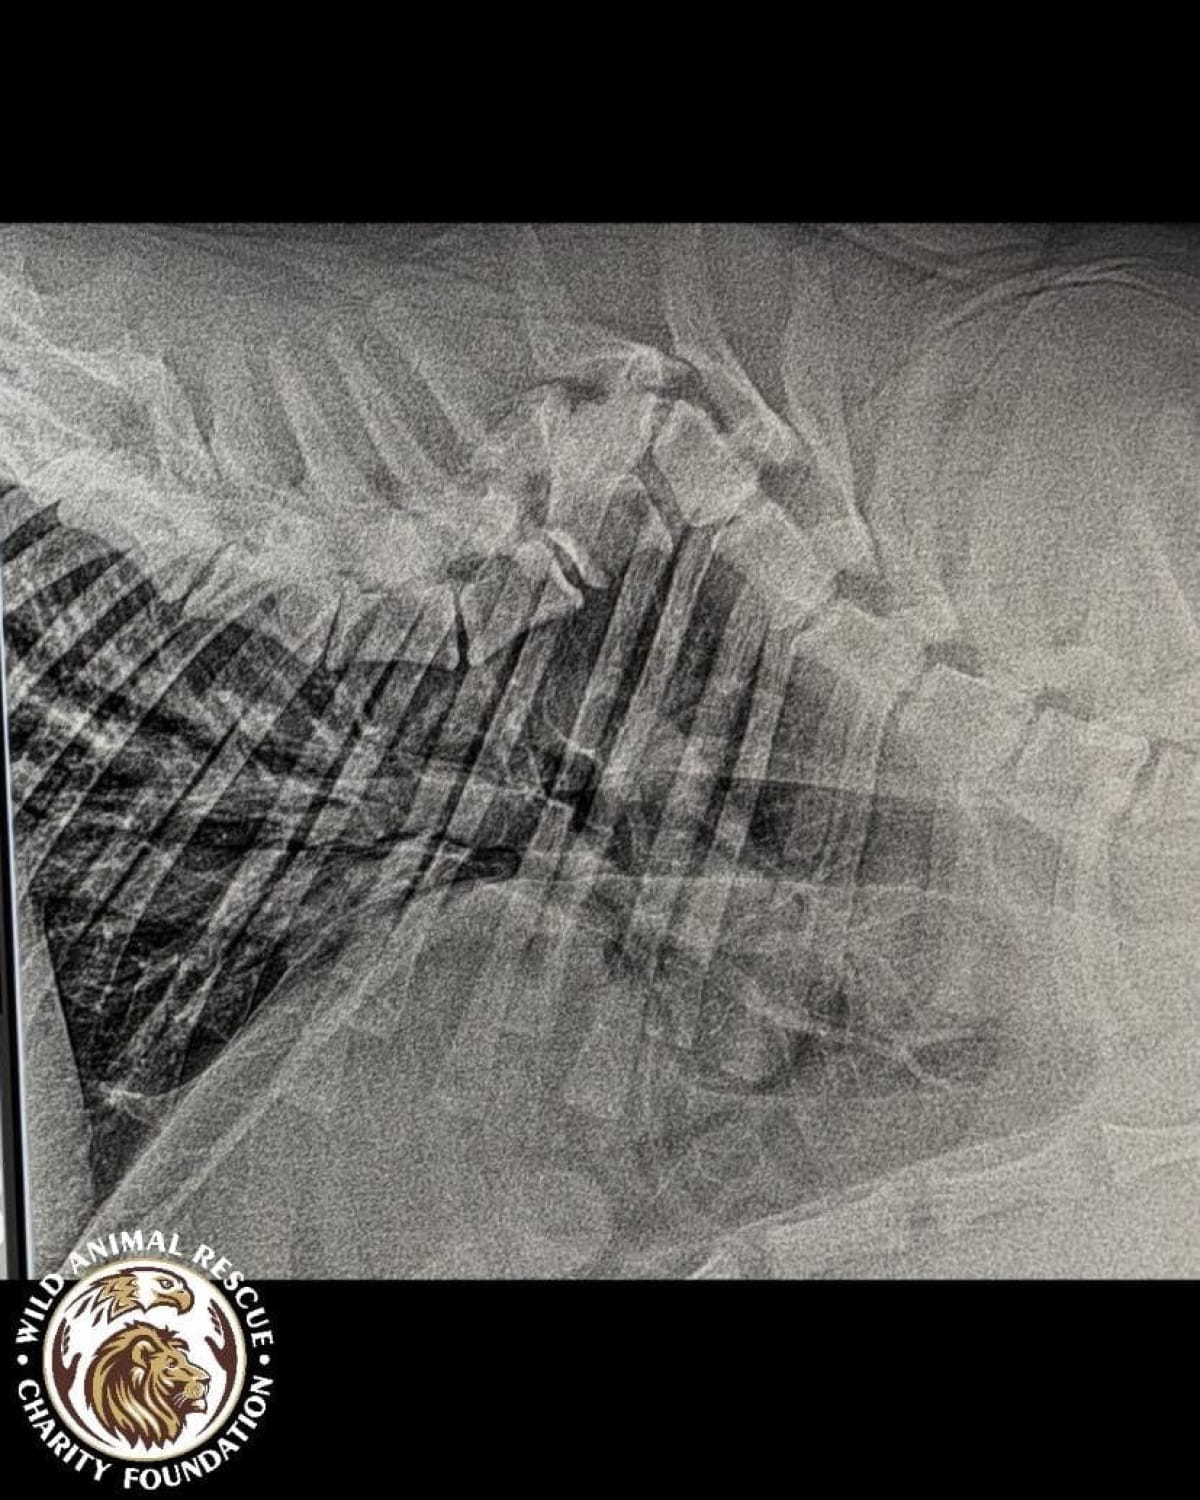

Тварині лише рік, але вона вже стала глибоким інвалідом. Тигриця не здатна самостійно підвестися і ледве пересувається, спираючись виключно на передні лапи. Після ретельного обстеження ветеринари були шоковані станом кісток молодого хижака.

• Критична атрофія м’язів та рахіт.

• Дегенеративні зміни у хребетному стовпі.

• Загальна деформація кісток скелета.

• Двобічна дисплазія кульшових суглобів.

• Остеоартроз та патологічне ремоделювання головки стегнової кістки.